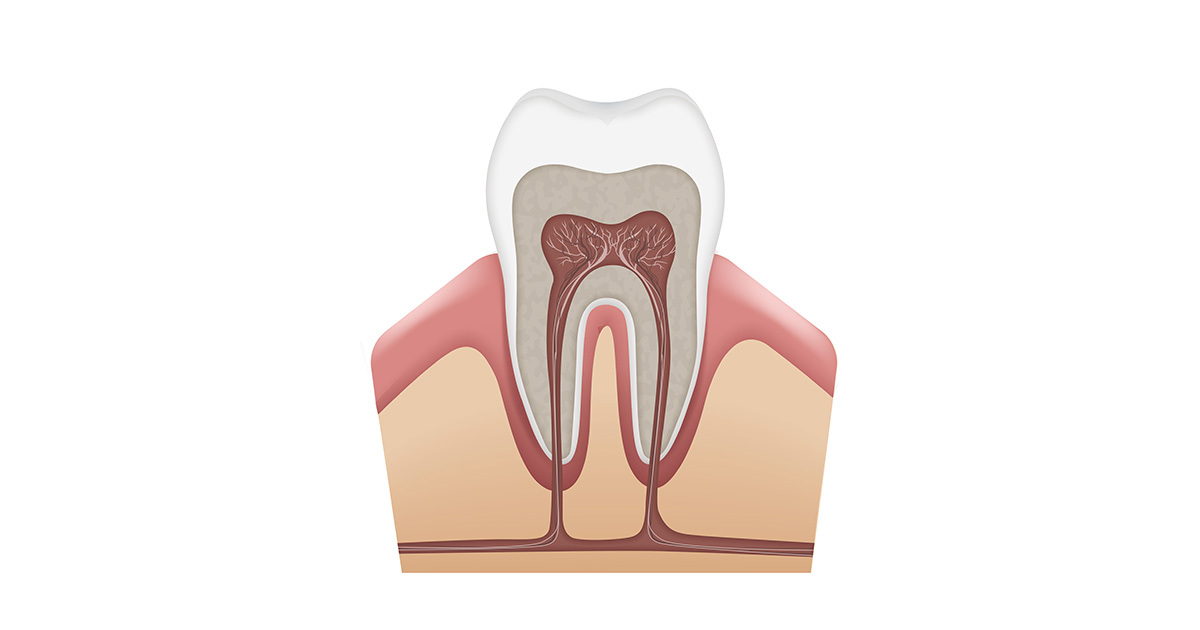

How Is Root Canal Diagnosed . root canal treatment is usually successful at saving the tooth and clearing the infection. a root canal is performed when the endodontist removes the infected pulp and nerve in the root of the tooth, cleans and. a root canal is a procedure that treats a tooth's nerve. root canal treatment (endodontics) is a dental procedure used to treat infection at the centre of a tooth. a root canal (endodontic therapy) is a dental treatment for infections in tooth pulp, the innermost layer of your teeth. What are the signs that a root canal is needed? Read about root canal cost, pain, symptoms, signs, and recovery. Molars, may have 2 to 4 canals, premolars typically have 1 to 2 canals (but may have three at times), cuspids may have 1 to 2 canals, and finally, incisors generally have 1 canal. human teeth may have one to four root canals, depending on the anatomy of the tooth. Learn about the root canal procedure. why does tooth pulp need to be removed?

a root canal (endodontic therapy) is a dental treatment for infections in tooth pulp, the innermost layer of your teeth. Learn about the root canal procedure. Molars, may have 2 to 4 canals, premolars typically have 1 to 2 canals (but may have three at times), cuspids may have 1 to 2 canals, and finally, incisors generally have 1 canal. why does tooth pulp need to be removed? What are the signs that a root canal is needed? root canal treatment (endodontics) is a dental procedure used to treat infection at the centre of a tooth. a root canal is performed when the endodontist removes the infected pulp and nerve in the root of the tooth, cleans and. a root canal is a procedure that treats a tooth's nerve. human teeth may have one to four root canals, depending on the anatomy of the tooth. root canal treatment is usually successful at saving the tooth and clearing the infection.